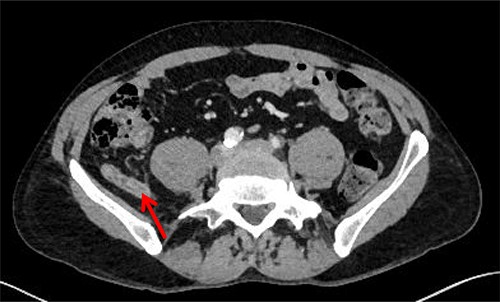

The patient was re-admitted and examination revealed a soft abdomen with localized rebound tenderness in the right iliac fossa. A computed tomography (CT) abdomen was requested and a referral made to the surgical team. The CT scan illustrated AA with the appendix located posterior to the ileo-psoas muscle (Figs 1–3). A diagnostic laparoscopy was performed, which revealed the head of the inflamed appendix herniated posterior to the psoas muscle in a cavity, (~25 mm deep and 10 mm in diameter) that could not be dissected laparoscopically (Fig. 2). Therefore, an uncomplicated open appendectomy was performed and the patient was admitted for post-operative observation. Recovery was uneventful and the patient was discharged without follow-up.

Coronal CT image. Inflamed appendix (red arrow) positioned between psoas (yellow triangle) and iliacus muscles (green star).